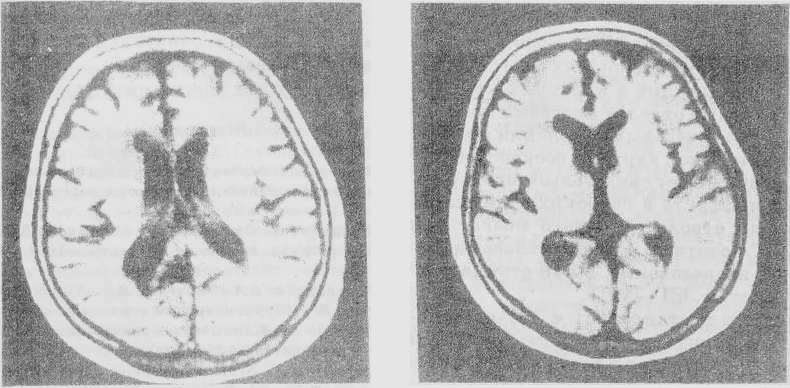

Рис. 1. Магнитно-резонансная томограмма (Т2-взвешенное изображение) больной 67 лет с очаговой ишемией мозга на фоне дисциркуляторной энцефалопатии. Резко выраженный лейкоарайоз в перивентрикулярной области

Большую диагностическую проблему представляет выявление при КТ и МРТ постишемических изменений мозга в виде лейкоарайоза (рис. 1) и так называемых “молчаливых” инфарктов, протекающих клинически скрыто (рис. 2). Нами не выявлено линейной зависимости между степенью лейкоарайоза (слабая, умеренная, выраженная) и клинической тяжестью церебрального сосудистого процесса.

Поэтому мы не разделяем мнения тех авторов, которые считают лейкоарайоз морфологическим маркером сосудистой деменции [10], хотя и не отрицаем его роли как предиктора (показателя возможности) появления у таких больных когнитивных нарушений. Гораздо большая роль в возникновении когнитивных расстройств и внезапном углублении очаговых неврологических симптомов принадлежит, по нашим данным, декомпенсации старого очага, то есть “немого” инфаркта (рис. 2).

Рис. 2. Магнитно-резонансная томограмма (Т2-взвешенное изображение) той же больной. Отчетливо видна постинфарктная киста в правой затылочной доле (“немой” инфаркт)